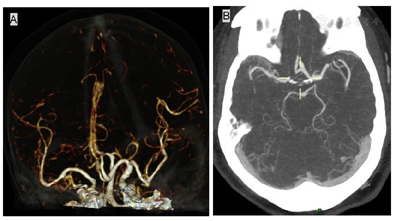

双侧锁骨下动脉管腔未见明显异常,双侧椎动脉起源未见异常,呈均衡型。Willis环不完整,后交通动脉未见显示。右侧大脑前动脉A1段缺如(图3A~B),双侧大脑前动脉A1段共干,血管显示清晰,以远管腔未见狭窄。

主动脉夹层(aortic dissection,AD )是由于各种原因导致的主动脉内膜、中膜撕裂,主动脉内膜与中膜分离,血液流入,致使主动脉腔被分隔为真腔和假腔。典型的主动脉夹层可以见到位于真、假腔之间的分隔或内膜片,真、假腔可以相通或不通。血液可以在真、假腔之间流动或形成血栓。术前应充分复习患者病史及影像学资料,主动脉夹层的影像学检查目的是要对全主动脉进行综合评价,包括AD受累的范围、形态、不同部位主动脉的直径、主动脉瓣及各分支受累情况、与周围组织的关系,以及AD的其他相关表现如心包积液、胸腔积液及脏器缺血情况等[1]。具体如下:(1)明确内膜片;(2)明确内膜破口的位置;(3)识别真腔与假腔;(4)明确AD的累及范围;(5)明确主动脉窦、主动脉瓣累及情况;(6)主动脉一级分支受累情况及血流状态;(7)识别主要脏器的缺血情况;(8)识别心包积液、胸腔积液及程度;(9)识别主动脉周围出血与否;(10)识别扫描野内其他脏器的病变及性质。术前脑血管CTA可明确颅底动脉环(Wills环)的完整性及大脑血供情况,为术中选择合适的脑灌注方式提供依据[2,3],本病例中Willis不完整,行体外循及麻醉术时,需要明确其变异情况。